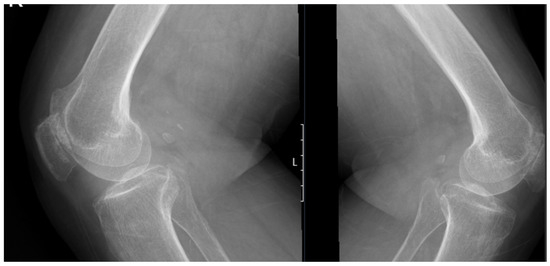

The surgical procedure was otherwise uneventful, and the patient was discharged after three days, a shorter stay than the previous hospitalization. Postoperative imaging confirmed proper positioning of the prosthesis (Figure 6), and the patient was referred to a home-based rehabilitation program, maintaining full ambulation. Pathological examination of the right knee specimens revealed:

Figure 6.

Standing anteroposterior X-ray of both knees taken one month after right total knee arthroplasty and eight months after left total knee arthroplasty. Both prostheses are well-positioned, with maintained alignment and no radiographic signs of complication.

The patient continued to be followed after the initial postoperative period. At the latest follow-up, 10 months after the left and 3 months after the right TKA, there was no radiographic evidence of prosthetic loosening, and the patient demonstrated satisfactory functional recovery, with improved mobility and reduced joint pain. No new or progressive systemic manifestations of alkaptonuria were reported during this period. Follow-up is ongoing to monitor for late complications and systemic sequelae.